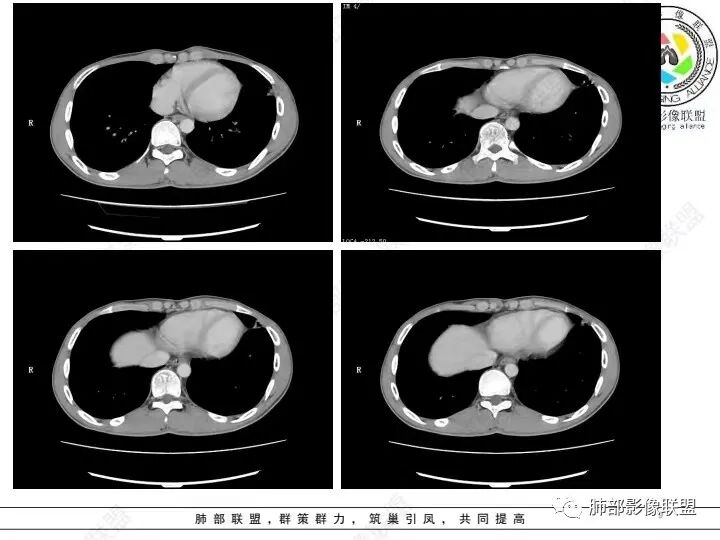

2021-7-14

2021-8-28

2021-9-2增强

1、临床特点:21岁男性,两天以前受凉后出现咳嗽,无明显咳痰,没有发热,有左胸痛,化验白细胞不高,降钙素原升高。C反应蛋白明显增高,结核抗体阴性。

2、影像特点:右肺中叶、左肺下舌段可见支扩。左肺下舌段及两肺下叶可见片状实变影及发结节影,病灶边界多显示不清,纵隔窗显示病灶密度较均匀,未见液化、空洞或钙化。左肺下叶部分病灶沿支气管分布,并可见局部支气管管壁增厚。